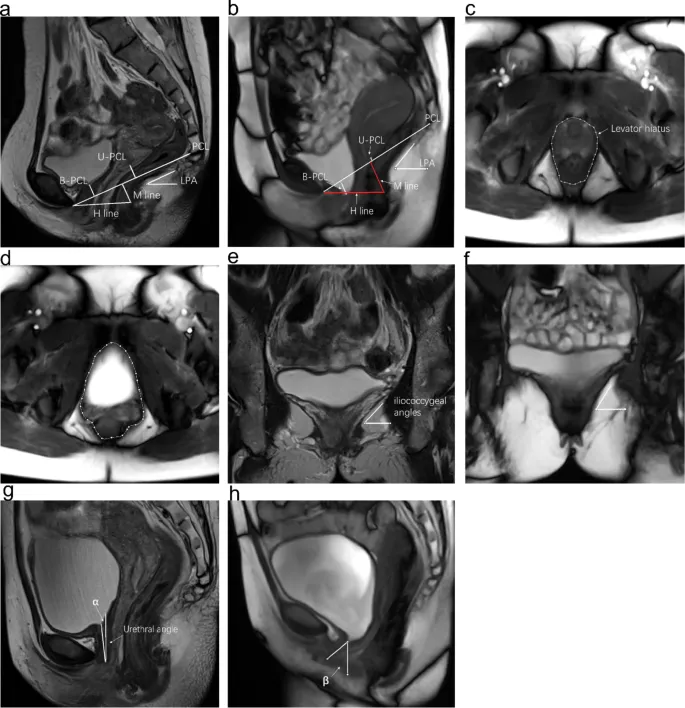

The field demands integration of urodynamic parameters (detrusor pressure >15 cmH₂O, maximum flow rate >15 mL/sec, post-void residual <100 mL), imaging findings (bladder neck descent >10mm, cervical descent >6cm below ischial spines), and functional assessments (Pelvic Floor Distress Inventory scores >95, quality of life impact scores >33).